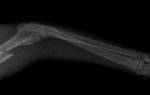

Перед лечением вывиха лапы или растяжения связок у собаки ветеринар проводит осмотр и, при необходимости, назначает рентген. В некоторых случаях может потребоваться МРТ.